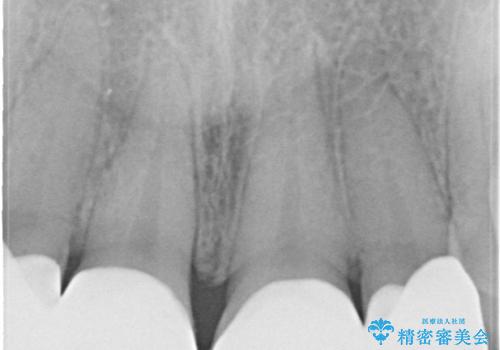

- 前歯をきれいにしたいとのご希望がありました。

生まれつき歯の色が白濁しているところや、黄色くなっているところがあり、セラミッククラウンに審美的改善を行うこととしました。